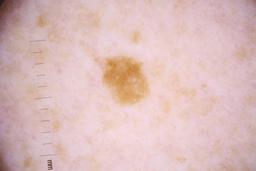

ISIC_4077341

- Challenge 2020: Training

- IP_1969685 IL_9238622

Clinical

| Field | Value |

|---|---|

| acquisition_day | 1 |

| age_approx | 50 |

| anatom_site_1 | Trunk |

| anatom_site_2 | Anterior trunk |

| concomitant_biopsy | False |

| dermoscopic_type | contact non-polarized |

| diagnosis_1 | Benign |

| diagnosis_confirm_type | serial imaging showing no change |

| family_hx_mm | False |

| image_type | dermoscopic |

| lesion_id | IL_9238622 |

| patient_id | IP_1969685 |

| personal_hx_mm | True |

| sex | male |